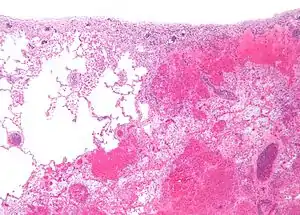

| Micrograph of a pulmonary infarct (right of image) beside relatively normal lung (left of image). H&E stain. | |

- Red infarctions (hemorrhagic infarcts) generally affect the lungs or other loose organs (testis, ovary, small intestines). The occlusion consists more of red blood cells and fibrin strands. Characteristics of red infarcts include:

- Lung: Pulmonary infarction or lung infarction